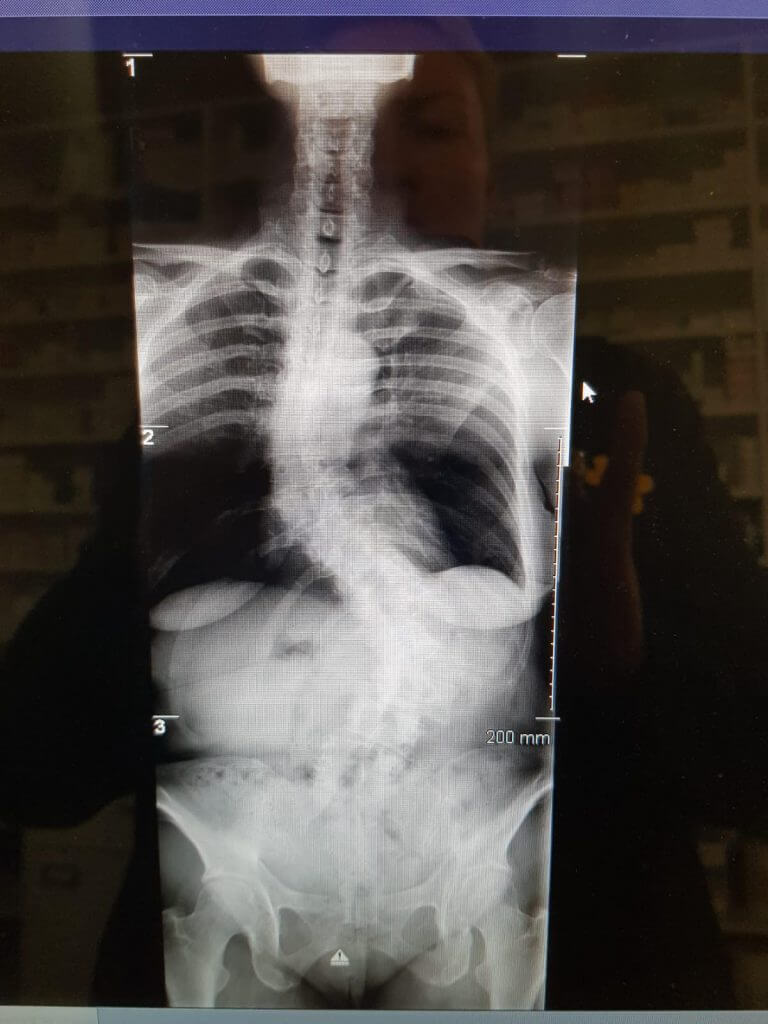

This patient has been seen by ScoliosisUK ltd Physiotherapist since 2013 when the patient was just 6 years old. This is not an idiopathic case – this is a non-idiopathic case – the cause is thought to be a post-operative rib fusion on the right side causing a large left thoracic curve on the left. The original cobb angle was around 50 degrees, and the family were desperate for this patient, who already had complex surgery as an infant, obviously wanted to avoid growing rods or fusion. This patient was provided with a NHS Boston and Cheneau derivatives initially and then finally several Gensingen Cheneau brace from 2016 and has managed to avoid surgery – now she is 15 years old with a 35-degree thoracic cobb angle. It’s been a tricky case as the consultant surgeon did not want to separate the ribs, which would have allowed for more cobb angle correction as the fusion of ribs prevents this, but this girl is a fighter, and she is now becoming a thriving young woman. She has had sharp bursts of support Schroth Best Practice home programs over the years in 6-12 week amounts to help with her shortened muscles and scar tissue, mum and dad both supportive. Her final Gensingen brace is being fitted shortly and we hope to see further signs of maturity on her X-ray to allow for part time hours this year, we all have everything crossed to see bony maturity and allow more weaning from brace sometime soon.

‘Non-idiopathic case – 6-year-old juvenile scoliosis thought to be a consequence of previous surgery and ultimately ribs fusing together. She reversed the curve from above 50 to 39 degrees cobb angle and holding strong at age 15’